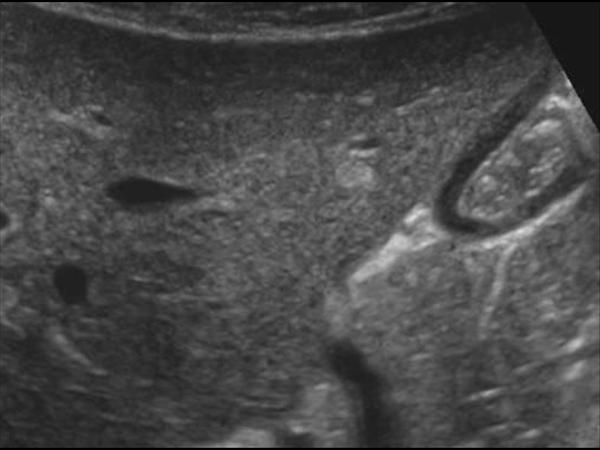

Gan nhiễm mỡ

Gan nhiễm mỡ - Ảnh 3

» Thông tin: Nữ giới – 56 tuổi.

» Lâm sàng: Kiểm tra sức khỏe.